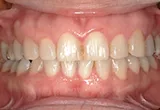

| 年齢/性別 | 60代女性 |

| 主訴 | 前歯が前に出てきた |

| 治療内容 | 全体的に歯周病やむし歯、根の治療(ヘミセクション)を実施。右上の歯にはサイナスリフト術を行い、骨の回復を待った後、半年後に2本のインプラントを埋入しました。 |

| 治療期間 | 9か月 |

| 費用 | 1,298,000円税込 |

| リスク・副作用 | 炎症反応によって術後に腫れや副鼻腔炎が生じることがあります。その程度は、手術の範囲や方法によって異なりますが、多くの場合、時間の経過とともに徐々に治まります。

ごく稀に、下顎奥歯の外科手術後に、唇や顎に痺れを感じることがあります。 |